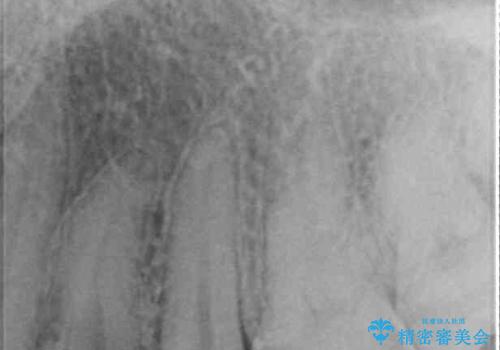

左上奥と右下奥に治療中の歯があり、虫歯を取っている途中で仮詰めの材料が充填されている状態でした。

仮詰め材を外すと虫歯が残っていたので、全てを取り除いた後に、ゴールドインレーの型どりを行いました。

当初はセラミックインレーによる修復治療を希望されいましたが、カウンセリングの結果、審美性よりも安定性を優先され、PGAインレー(ゴールドインレー・白金加金合金インレー)による治療を行うこととしました。